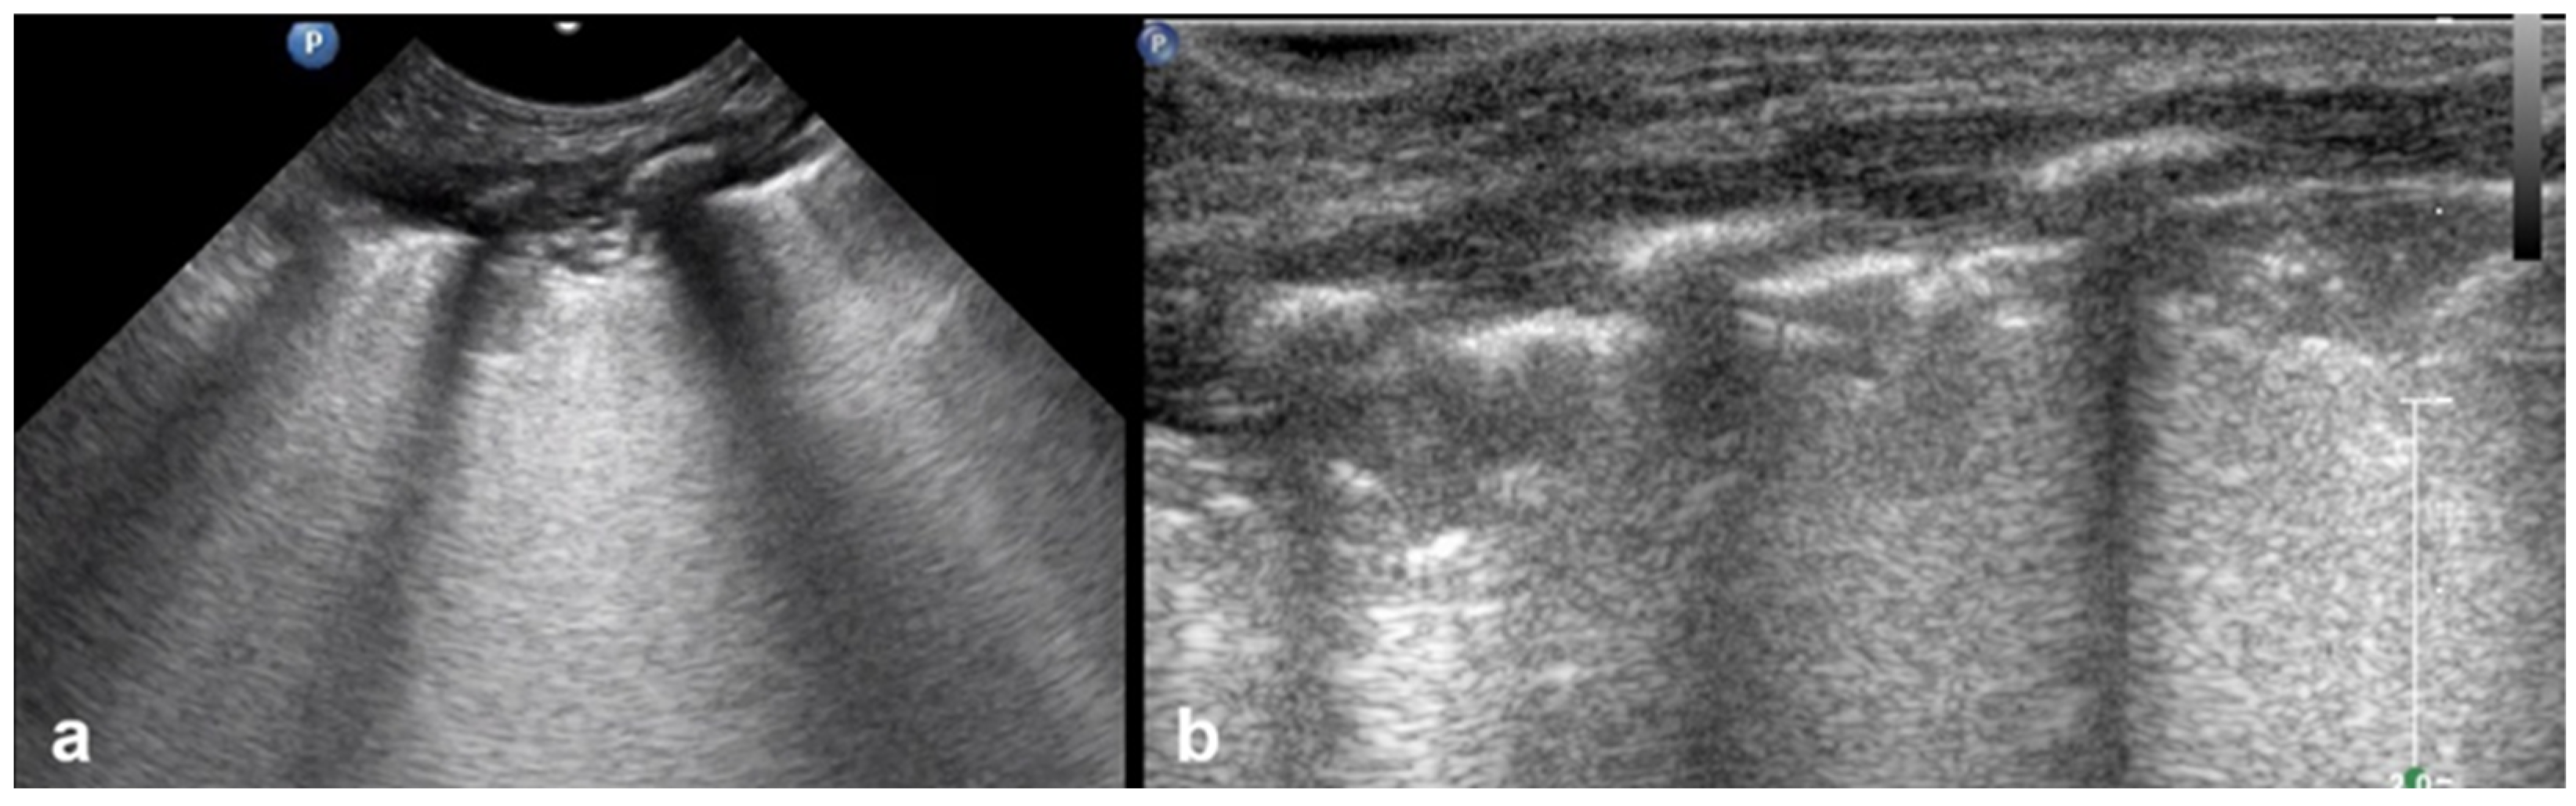

3.1.5. Sea-Shore Sign

The “sea-shore sign” is a characteristic ultrasound finding observed during M-mode (motion mode) scanning, and is indicative of normal lung sliding. In this pattern, the pleural line and overlying chest wall structures produce a series of horizontal echogenic lines, representing static tissues (Figure 6).

Figure 6.

Upper image: LUS with normal A-Lines in B (bright)-mode. The simultaneous M (motion)-mode image (lower image) reveals series of horizontal echogenic lines which represent the pleural line and its reverberations (A-lines), as well as the air-filled alveoli with a granular/sandy appearance (more prominent in real time scan). These in combination produce the seashore sign.

In contrast, the underlying lung parenchyma, which moves in synch with respiration, generates a granular or sandy appearance due to the dynamic motion of air-filled alveoli [17]. This combination creates the visual effect of waves (static layers) above and sand (with a dynamic speckled texture) below, thus producing the so-called “sea-shore sign”. The presence of this sign confirms normal apposition and movement of the visceral and parietal pleurae, and can be used to effectively rule out pneumothorax at the examination site. The “sea-shore sign” is considered to be a reliable and non-invasive indicator of intact lung sliding, and is frequently used in both adult and neonatal lung ultrasound to assess respiratory function and pleural integrity [5,6,15,22,23].

When this sign is absent, uniform horizontal straight lines, known as the stratosphere sign or “barcode sign”, appear, indicating pneumothorax as a possible cause [18,24].